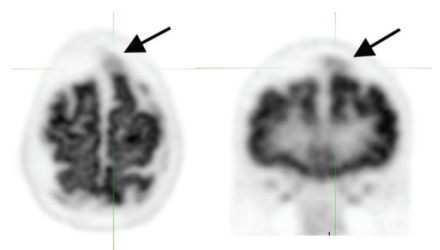

atrophy –> sulcal widening –> artifact of hypometabolism (pitfall for misdiagnosis of neurodegenerative disorder)